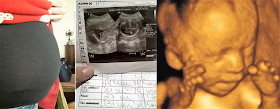

La panza de Mayra, su primera ecografía y un bebé de 27 semanas de gestación

Hace unos días Mayra tuvo su primera ecografía y supo que se trata de un bebé. Estaba feliz de ver a su hijo por primera vez. Piensa llamarlo Ian. Además, la fecha coincidió con el aniversario del fallecimiento de su madre, ocurrido hace apenas un año. Pensó que se trataba de una feliz coincidencia, pues el dolor de haber perdido a su madre quedaba paliado con la presencia de esa vida en su seno y el latido de ese corazón palpitante que oía por primera vez en su interior. De hecho, una vez escuchó los latidos del corazoncito de su bebé ya no tuvo ninguna duda de que debía seguir adelante con el embarazo.